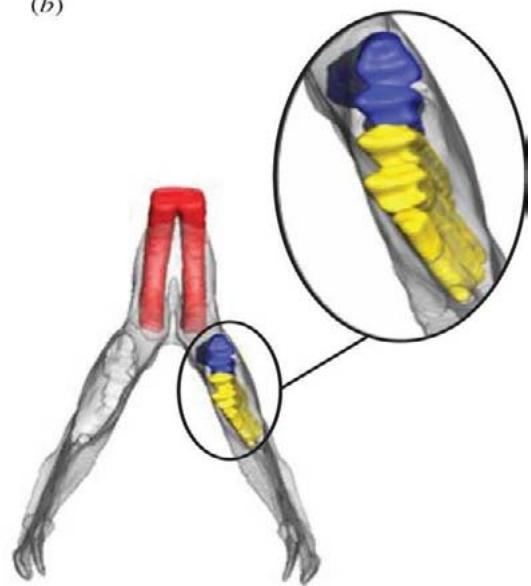

O exame da cavidade oral de roedores e coelhos domésticos faz parte de todo exame físico e é muito importante para o diagnóstico da síndrome do desgaste dentário inadequado, que leva ao hipercrescimento dentário e consequentemente a problemas sistêmicos, no entanto, o exame oral em um animal consciente fornecerá apenas informações limitadas. O exame oral definitivo só pode ser realizado sob anestesia geral SOARES, Helena Baggio (2018). Tem havido inúmeras publicações nas últimas duas décadas descrevendo alterações patológicas específicas observadas nas diferentes espécies. Muitos deles apontam a importância de um exame radiográfico completo do crânio usando múltiplas visualizações e dão alguns conselhos úteis sobre o tratamento, como o uso de linhas de referência anatômicas que simplificam muito a explicação dos problemas bucais aos proprietários do animal (Fig. 2 e 3), pois eles podem ver claramente a extensão das alterações. Isso permite que eles entendam melhor as recomendações de tratamento e quaisquer complicações associadas BOEHMER, E (2009). Ao incluir a radiografia como ferramenta diagnóstica, o número de pacientes relatados que sofrem de má oclusão causada por diferentes alterações periodontais e dentárias patológicas chega a até $88\%$ da população clínica geral BOEHMER, Christine (2020).

Fig. 2: Linhas de referência anatômicas radiográficas de um coelho clinicamente saudável. Vista Latero Lateral.

Foi realizado a coleta de sangue para exames laboratoriais e o paciente foi encaminhado para estudo radiográfico do crânio, onde foi requisitado três projeções a saber: rostro caudal, ventro dorsal e latero lateral (Fig. 8, 9 e 10) e analisado de acordo com BOEHMER, E, 2009 as linhas de referência anatômica para a espécie fechando o diagnóstico de má oclusão dentária pordesgaste ineficiente.

Fig. 8: Radiografia de crânio projeção rostro caudal. Visualização de pontas dentárias evidenciadas pelas setas vermelhas Fig. 9: Radiografia de crânio projeção dorso ventral. Leve desalinhamento dentário na borda medial do ramo mandibular direito, sobrepuljando a linha de referência anatômica amarela, evidenciado em vermelho Fonte: Arquivo pessoal do autor Fig. 10: Radiografia de crânio projeção latero lateral visualização de crescimento dentário dos pré molares e molares sobre a mesa oclusal (linha amarela ${ \mathsf { n } } ^ { \mathsf { o } } \ { \mathsf { 1 } } \ -$ traçada do início do palato duro ao terço inferior da bula timpânica) e também visualização de crescimento da coroa de reserva acima da linha amarela $\mathsf { n } ^ { \circ } \mathsf { \Lambda } _ { 2 } ^ { }$ que vai do osso nasal ao osso occipital (sugerindo crescimento retrógrado), evidenciado pelas setas vermelhas.